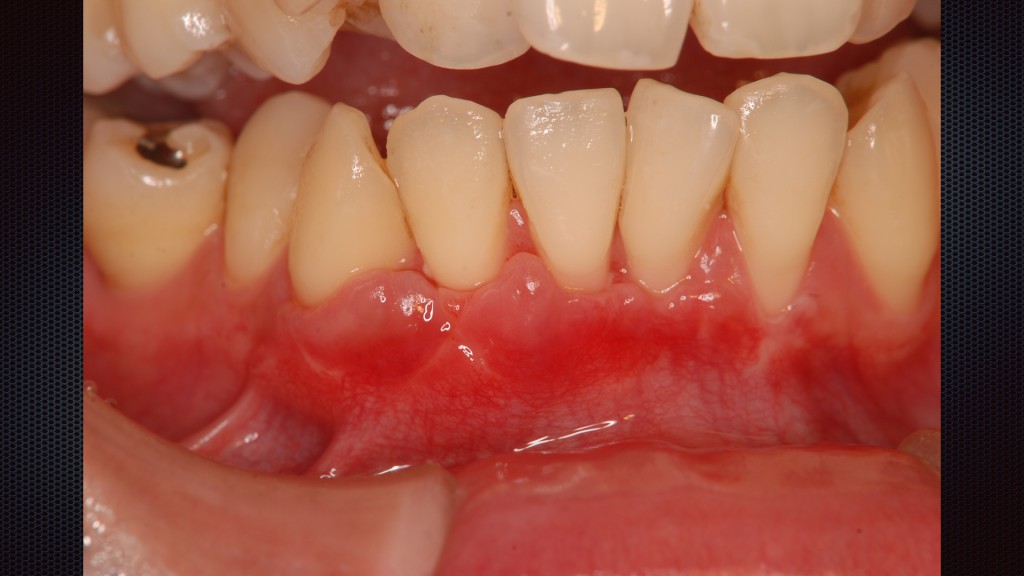

Ⅰ期 歯肉炎

歯周ポケット3mm以内

歯周病菌の出す毒素などで歯茎に炎症がおこる。赤く腫れるが、見た目だけではわからないこともあります。